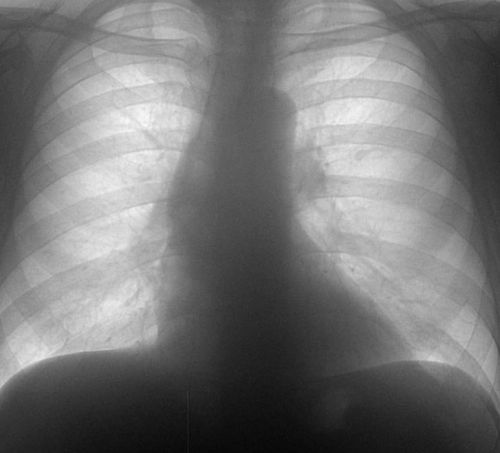

Фото флюорографии здорового человека — рисунок легких в пределах нормы

Во время прохождения ФЛГ, через человеческое тело пропускаются рентгеновские лучи в количестве 0,05 миллизиверт. Это мизерная доза с допустимой нормой облучения, которая может помочь спасти здоровье. При помощи флюорографического обследования грудной клетки медицинские специалисты диагностируют:

На основании сделанных снимков врач назначает лечение. Вовремя начатая терапия иногда спасает человеку жизнь, а при диагнозе туберкулез, позволяет оградить от заражения других людей, посредством изоляции больного.

На заметку! Из всех видов рентгенодиагностики (КТ, рентгенография, рентгенограмма), флюорография является самой недорогой и малоинформативной. Она может «не заметить» мелких новообразований. Даже если с ее помощью удалось обнаружить очаг поражения, то для постановки точного диагноза требуется более детальный скрининг с помощью другого диагностического метода.